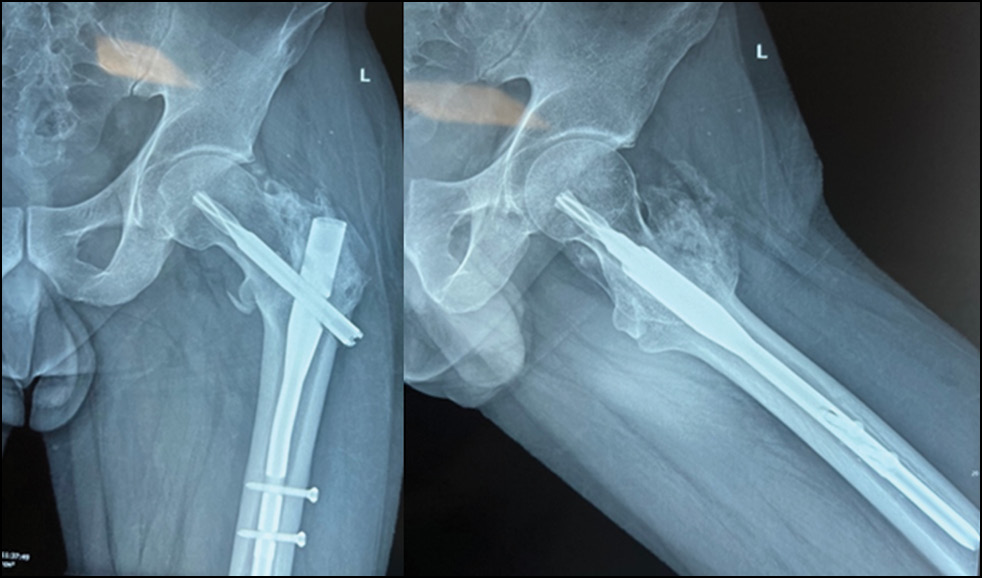

Рис. 5. Пациент 1: контрольные рентгенограммы спустя 6 месяцев после проведения последовательного остеосинтеза.

Fig. 5. Patient 1: follow-up radiographs six months after sequential osteosynthesis.

Рис. 6. Пациент 1: a — спустя 6 месяцев после операции, b — функциональный результат лечения.

Fig. 6. Patient 1: a, six months postoperatively; b, functional outcome of treatment.